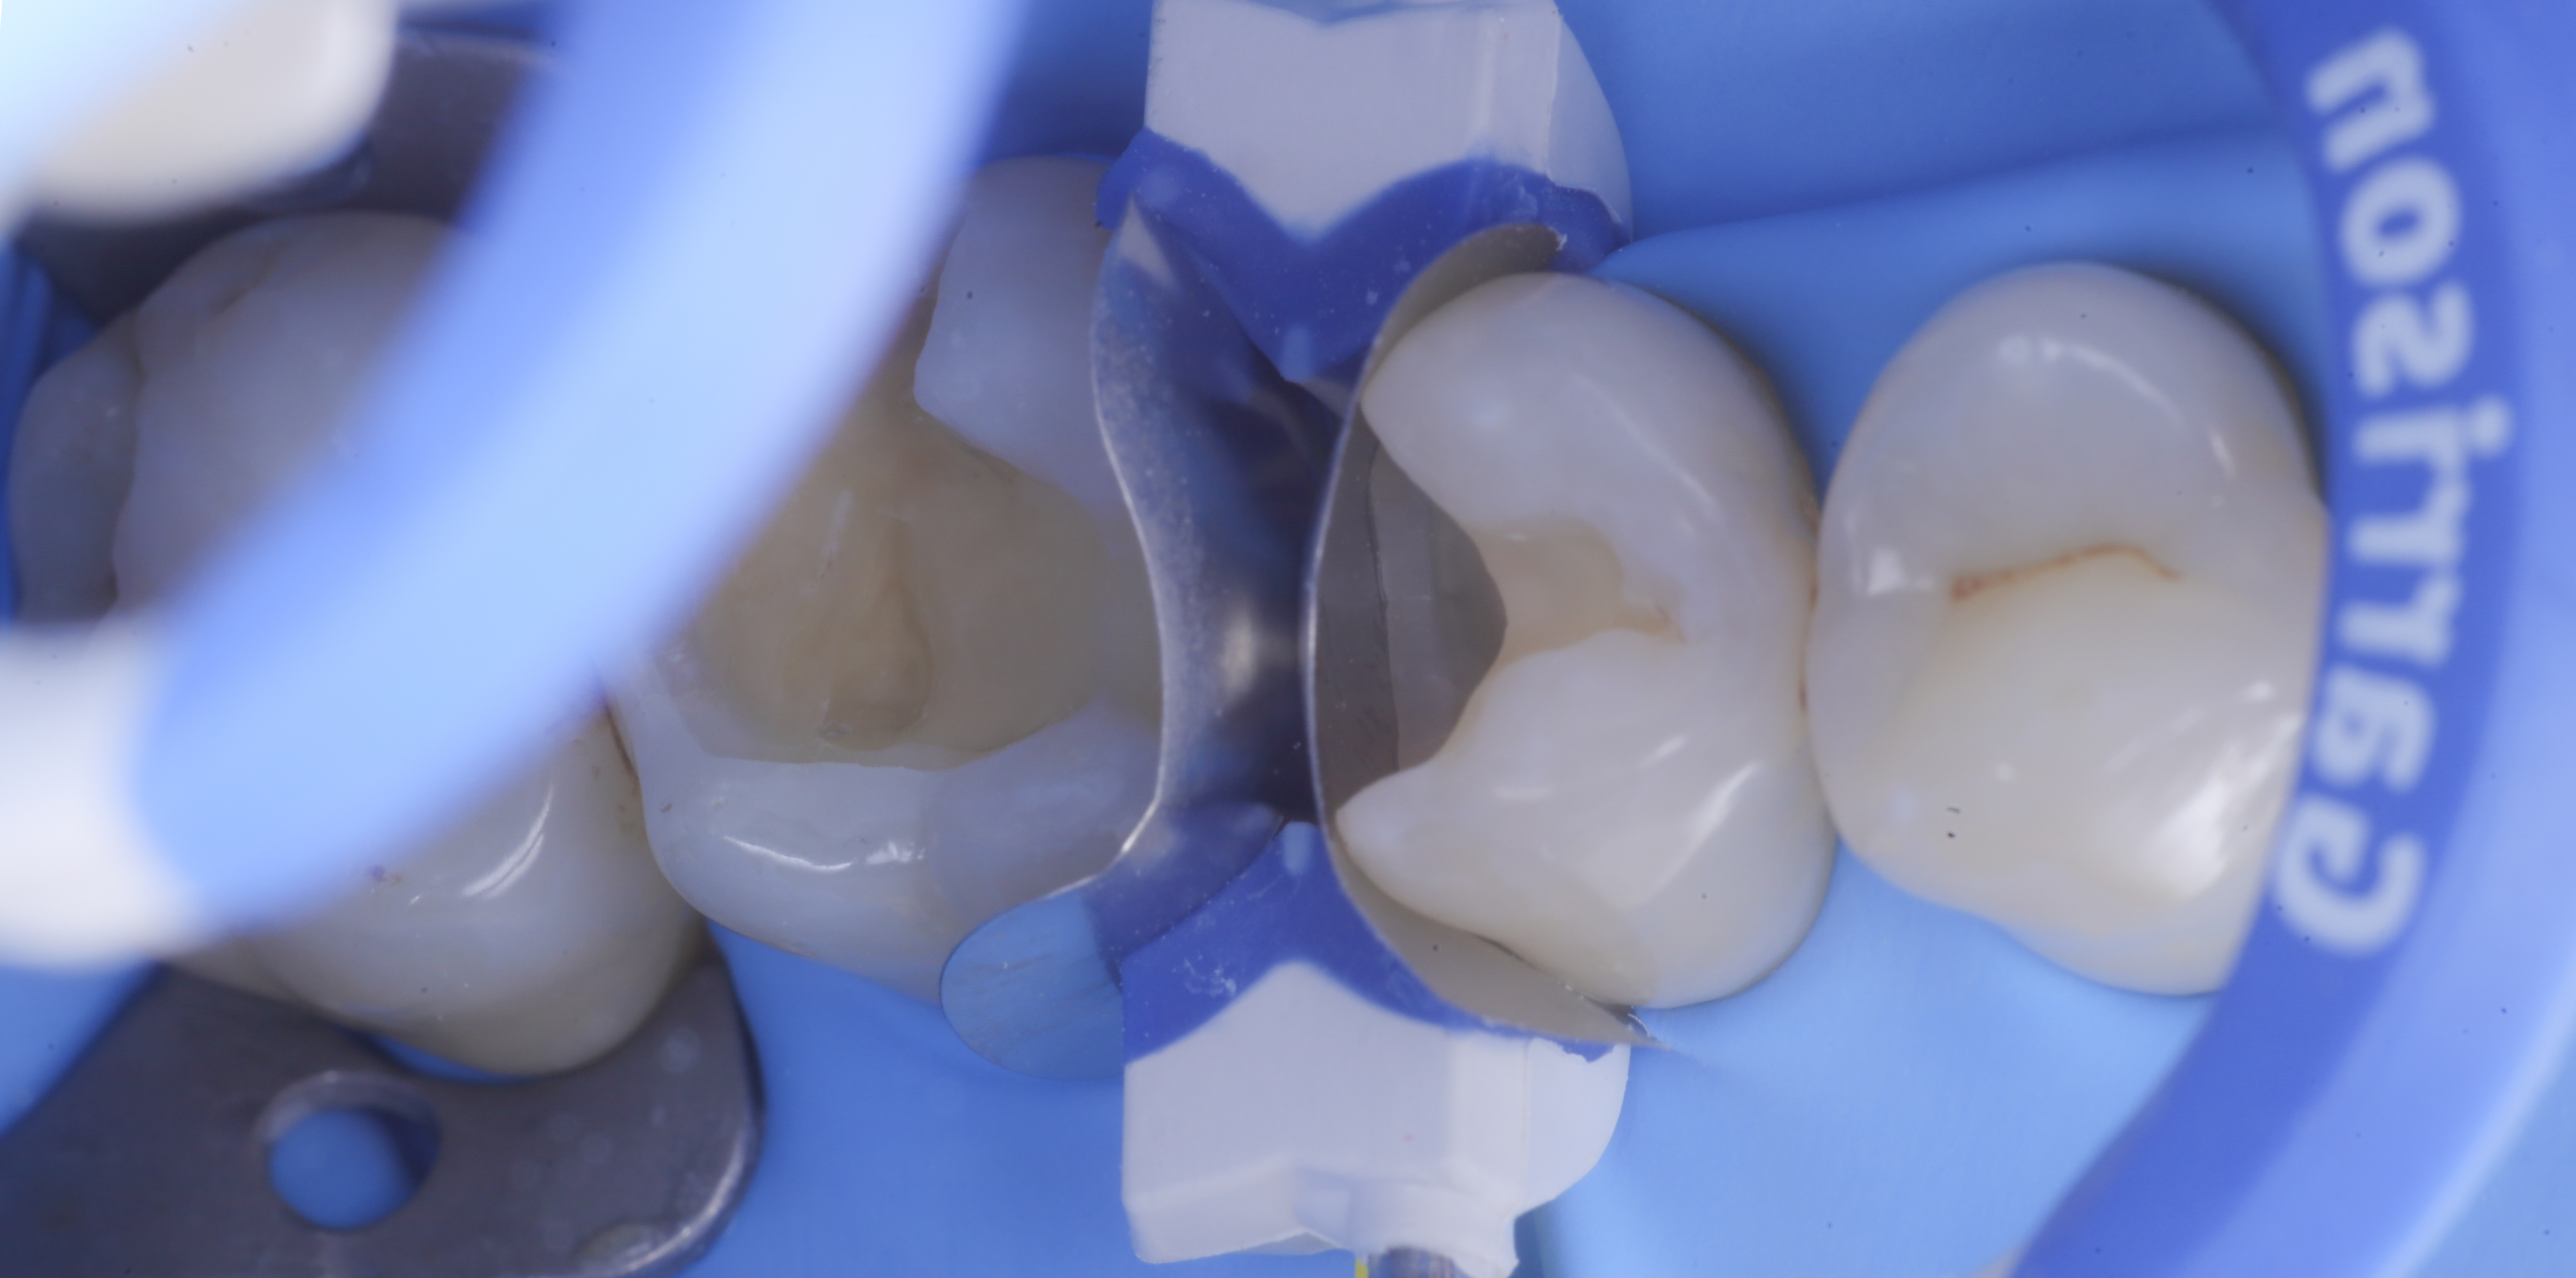

foto 2 Isolamento e aspetto delle cavità ultimate

foto 3 Aspetto vestibolare della cavità ultimate

foto 4 Aspetto della chiusura cervicale e sulle pareti assiali dato dalla prima matrice

foto 5 Aspetto della chiusura cervicale e sulle pareti assiali della seconda matrice

Una volta eliminato completamente il composito, si procede con la detersione della dentina con frese multilama ed alla rifinitura dei margini di smalto che dovranno essere robusti e puliti.

Dopo il posizionamento del cuneo, anello e delle due matrici sezionai, selezionate per altezza e raggio di curvatura, si procede con l’applicazione dell’adesivo universale, previa pre-mordenzatura dello smalto.